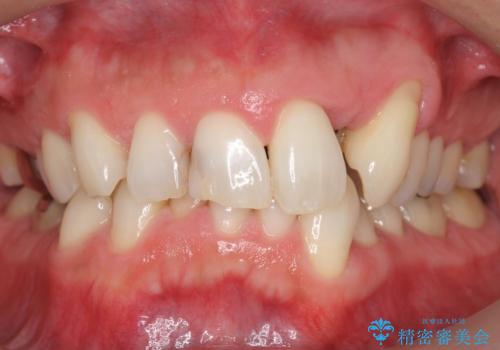

生まれつき歯が黒い テトラサイクリン歯 40代女性

- 生まれつき歯が黒いことを主訴に来院された患者様です。

小児期の抗生物質長期投与による歯質の変色(テトラサイクリン歯)だと推測されます。

患者様のご希望により、セラミッククラウンによる補綴治療を行いました。

矯正治療を併用した補綴治療を提案しましたが、ご予算と短期間での治療のご希望から補綴治療のみ行うこととなりました。

もともとの歯並びにより、歯茎のラインやクラウンの形態に限界があることをご理解頂いた上で治療を行いました。

もともとの歯並びにより歯茎のラインやクラウンの形態に限界がありましたが、主訴である歯の色が改善され喜んで頂けました。